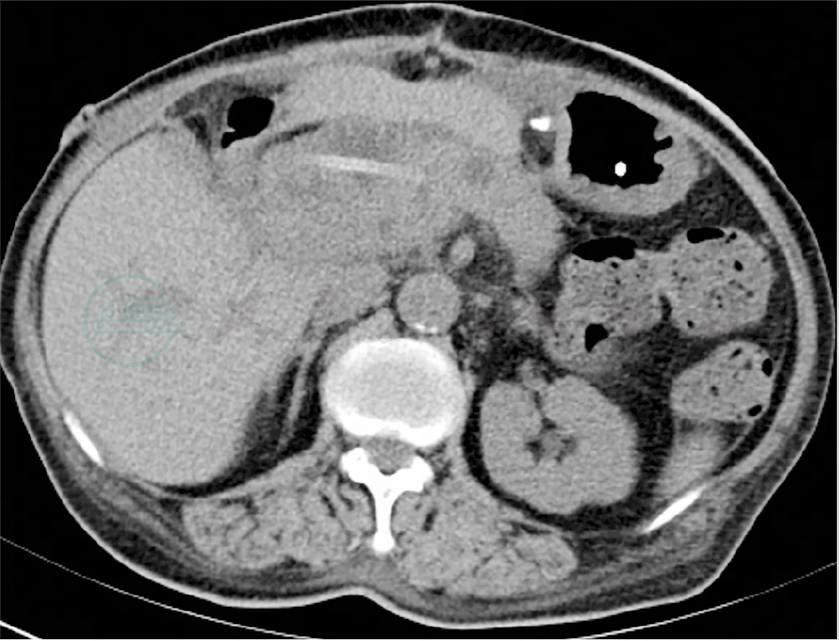

2020-03-15:当地医院腹部增强CT(图1~图3)示壶腹占位,大小约1.2cm×1.8cm,动脉期可见强化,肝内外胆管,胆总管及胰管扩张,胆总管最大内径约1.3cm,胰管最大径约0.5cm。当地医院血生化检查:白蛋白22g/L,总胆红素146μmol,直接胆红素102μmol。

图1 壶腹部占位

图2 胆总管扩张

图3 胰管扩张